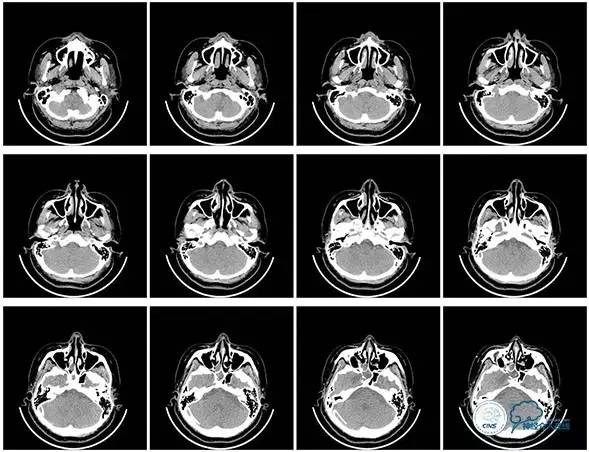

头颅CT

病史:患者于1年余前,因头部外伤在外院行头颅CT提示:未见异常。约3月后患者出现头痛、发作性意识丧失,在当地医院行头颅CT及MRI提示:未见明显异常。诊断为外伤性癫痫,予以对症治疗,未见明显好转。6月余前,无明显诱因出现鼻腔漏液,予以保守治疗,此后鼻腔间断漏液,漏液后头痛缓解。13天前因高热、恶心、呕吐在外院诊断为颅内感染(肺炎链球菌),予以抗炎等对症治疗2周后鼻漏停止,体温正常,CSF常规、生化正常,但头痛仍未缓解,转入我院神经内科治疗。反复腰穿颅内压450-500mmH2O左右,脑脊液常规及生化均正常。颅脑CT及MRI、MRV提示:左侧顶叶硬膜下血肿,鼻窦炎、乳突炎、左侧横窦、乙状窦闭塞、右侧横窦、乙状窦狭窄。予以华法林抗凝治疗2周,维持INR2-3,患者头痛仍无明显缓解,颅内压无降落,转入我科。

诊断:1、右侧横窦、乙状窦狭窄;2、硬膜下血肿(左侧顶);3、继发性癫痫;4、脑脊液鼻漏;5、颅内感染;6、乳突炎;7、鼻窦炎。

病理过程推理:首先是乳突炎—诱发左侧横窦乙状窦血栓最终闭塞,右侧横窦乙状窦狭窄—导致颅内高压,造成头痛及癫痫—持续颅内高压—皮层静脉回流受阻导致自发性硬膜下血肿及自发性脑脊液鼻漏—颅内感染。